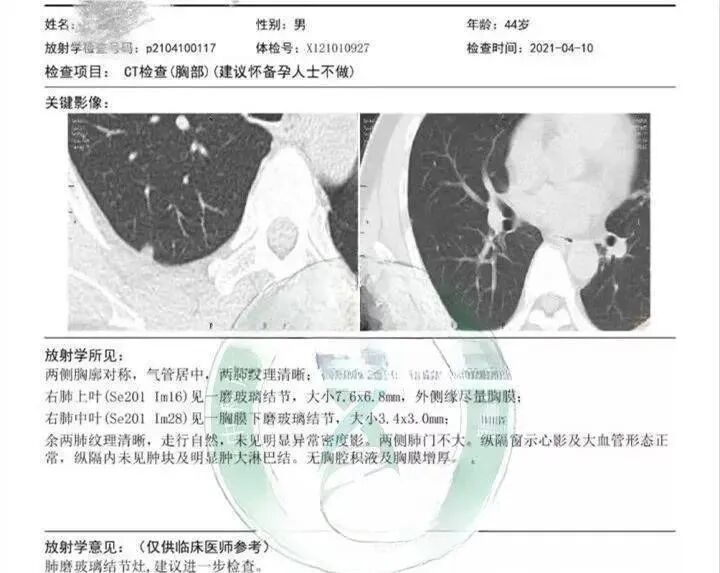

44岁的王先生经过体检,发现右肺脏层胸膜表面之下(肺的内部),存在两枚磨玻璃结节,其中较大者直径有7.6mm,医生建议随访。

图片